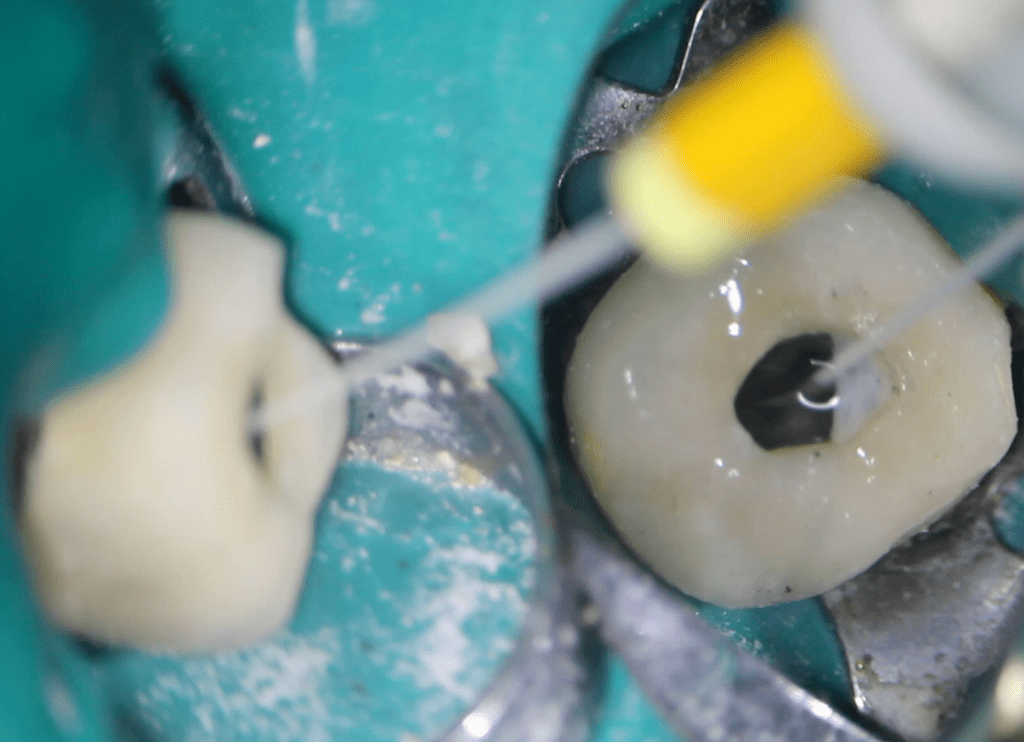

Pulpotomía biodentine + reco preendio